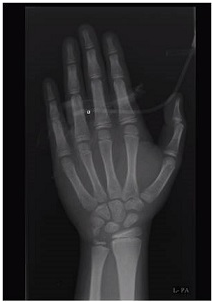

8. Bone age delayed; 8 years and 10 months at chronological age of 11 years 6 months (Figure 1).

9. Figure 1 Bone age delayed (8years and 10 months at chronological age of 11yrs 6 months).